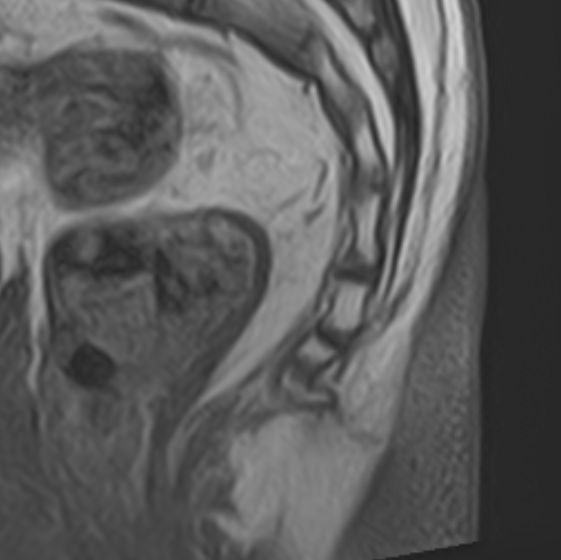

Боль в нижней части спины является наиболее распространенным симптомом различных заболеваний позвоночника, которые поражают пояснично-крестцовый отдел. В ряде случаев боли в нижних отделах спины сочетаются с кокцигодинией, то есть болями в рудиментарной части позвоночного столба – копчике. Причинами появления таких симптомов могут быть воспалительные процессы, дегенеративно-дистрофические заболевания позвоночника, опухолевые поражения данной анатомической области.

МРТ является наиболее информативным способом диагностики заболеваний позвоночника, так как позволяет оценить состояние костных структур позвонков, расположенную здесь часть спинного мозга с нервными корешками, а также связки, сухожилия и окружающие мягкие ткани. Магнитно-резонансная томография превосходит все другие методы диагностики не только по информативности, но и по безопасности, так как в основе метода лежит использование внешнего магнитного поля и отсутствует вредное для организма воздействие облучения, свойственное рентгену.